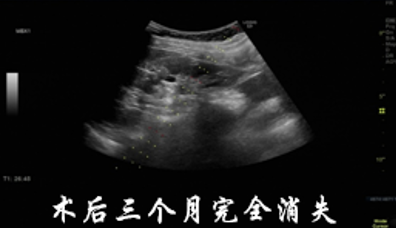

从急诊转诊到介入科就诊,再到住院检查、治疗、出院,整个流程无缝衔接。张奶奶上午办理住院后完成相关术前检查,下午就顺利接受了硬化治疗,术后颈部胀痛明显缓解,第二天各项指标平稳后便康复出院,全程仅用两天时间。